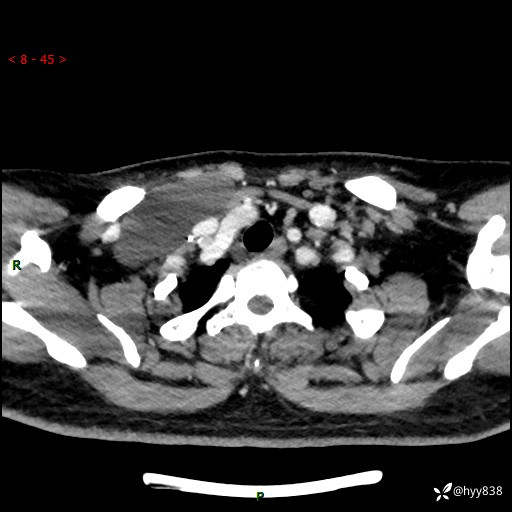

增强动脉期+静脉期